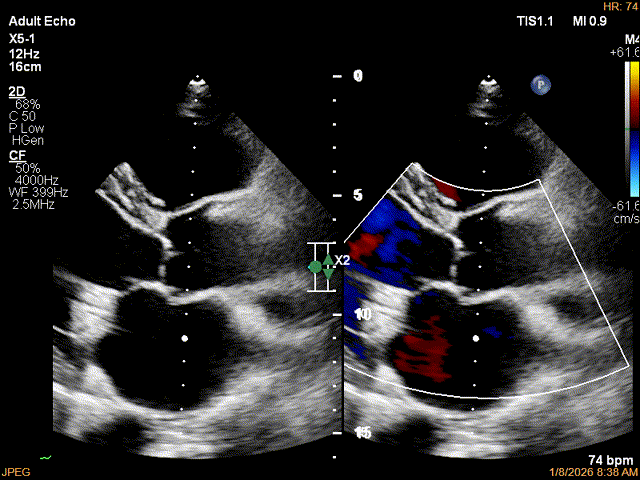

术后影像

最终结果3D-Zoom-color显示组织桥稳定,原脱垂区域前后叶对合部分的脱垂已消除,反流降至1+以下

夹子释放Bi-com切面显示残余反流情况

肺静脉收缩期逆流消失,频谱形态基本恢复正常

术后2D TTE:

术后TTE可见二尖瓣微量-轻度反流,三尖瓣反流明显改善降至中度